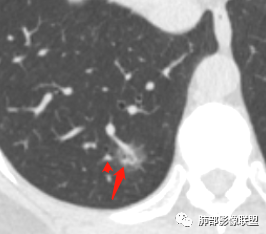

晨读:52f,体检发现右下肺结节,空洞、周围晕征(磨玻璃),局部血管影增粗,考虑1.真菌感染;2.GPA或不典型单发转移待排。

晨读:体检发现肺部结节,胸部CT:右下肺混合密度结节,结节中心空泡,壁光滑,结节边缘模糊,软毛刺,结节血管相对清楚,考虑良性结节可能,抗炎后复查。

右下肺混合磨玻璃结节,其内见空洞,空洞壁光滑,结节周围可见晕征,可见增粗血管,首次体检发现患者无症状,还是建议抗炎2周,1个月后复查,鉴别腺癌。

右肺下叶混合磨玻璃结节,边缘清晰,有分叶,毛刺,内见空泡。考虑腺癌。常规可以抗炎后复查。

体检发现肺部结节,右下肺混合密度结节,结节中心空泡,壁光滑,结节边缘模糊,血管在结节内增粗,矢状位前基底段还有一片磨玻璃影,所以考虑良性结节可能,炎性肉芽肿?抗炎后复查。腺癌合并炎性改变待排。

晨读病例,右肺下叶小结节病灶,内可见光滑空洞,周围可见边缘模糊磨玻璃影,首先考虑感染性病变,真菌或结核可能,鉴别腺癌,后者小病灶空洞少见,周围磨玻璃影清晰,胸膜凹陷征。

病灶大部分磨玻璃边界是模糊的,但有些地方还是比较清楚,腺癌是不能完全排除的,建议1个月后复查。

mGGO,周围有晕,边界不清,空洞,收缩力不强,血管通过走形正常,首先考虑炎性结节,抗炎和复查。筛查真菌。

内部低密度是空洞还是扩张的细支气管有疑问,边缘有的层面清楚有的层面模糊,恶性待排吧。

右肺下叶混合磨玻璃结节,边缘清晰,有分叶,毛刺,内见空泡。考虑腺癌。

我未见过的类型,CT征像良恶参半。女性,52岁,腺癌的好发人群。良性征像外周纯磨玻璃影很大,而且境界欠清晰。恶性征像,中央薄壁气囊边缘实性增厚,而而且厚薄不均匀。结合性别年龄,腺癌首先考虑,处理:随访3-6月,看看实性部分有无增多,应该不影响生存率。

磨玻璃结节,中央有空洞,周围晕征,磨玻璃血运明显,考虑腺癌,鉴别隐球菌。

晨读:结节伴晕,晕模糊,内有小空洞,周边还有片状模糊影,支持首先考虑炎性,临床会先抗感染治疗后复查。

晨读:右下肺结节,结节中心小空洞,壁光滑,结节周围有晕,边缘模糊,其他基底段亦可见斑片磨玻璃影,考虑炎性肉芽肿。隐球?寄生虫?

晨读:中老年女性,体检来诊。右肺下叶后基底段近胸膜下mGGN,其内实性成分似见毛刺及分叶,并见空泡征,周围GGO边界清楚,近肺门端见血管影伸入病灶并略显扩张,病变与支气管关系观察欠佳。多考虑恶性,腺癌可能性大。鉴于首次检查,常规建议抗炎治疗后复查,观察病灶变化情况,再决定下一步诊疗方向。

晨读,中老年女性,右下肺混合磨玻璃结节,边界模糊,内有空泡,张力高,考虑支气管扩张,周围血管相连,稍有增粗,考虑良性病变,细支气管扩张畸形并周围炎。腺癌待排。

晨读,女,52岁体检发现结节,右肺下叶见磨玻璃样结节影,边缘见毛刺,病灶内可见小空泡影,考虑腺癌可能,待除外炎性病变。

病灶内低密度像扩张的支气管,整体被病灶包围,可以定为空泡,PC没有这么大的牵拉,曲霉的话病变范围太小,而且是体检发现。病灶周围磨玻璃似清非清,病灶下缘磨玻璃是明确清晰的,因此诊断倾向于粘液腺癌,比较心虚的地方是没有抗炎复查。

右肺下叶后基底段混合型磨玻璃结节,边缘见晕征,内见小空泡/空洞,其内壁光整,与支气管关系不密切,常规考虑炎性肉芽肿病变,结核/隐球菌可能,腺癌待排,建议抗炎1月后复查。

右下叶后基底段混合密度结节,边缘磨玻璃模糊,晕征,中心实性成分似有多个小结节融合,收缩力不明显,中心空泡样改变内缘光滑,考虑小空洞,综合考虑良性炎性结节,隐球可能,结核与曲霉待鉴别。抗炎后复查或穿刺活检。

右肺下叶混合磨玻璃结节,中心有小透光区,壁光整,磨玻璃边缘模糊,收缩力不明显,考虑炎性结节,抗炎治疗后复查,代排隐球菌。

右肺下叶基底段胸膜下小结节,周围模糊晕征,其内光滑囊腔影,考虑小空洞,其内血管走形自然,周围软毛刺,常规考虑炎性结节,隐球可能性大,建议抗感染后复查,鉴别粘液腺癌。

从那么多天以来的读片结果看,不要走寻常路,各位老师考虑炎性的多,小隐球结节还是实性的多(见得少不知道对不对),空洞张力较高,那我考虑腺癌。